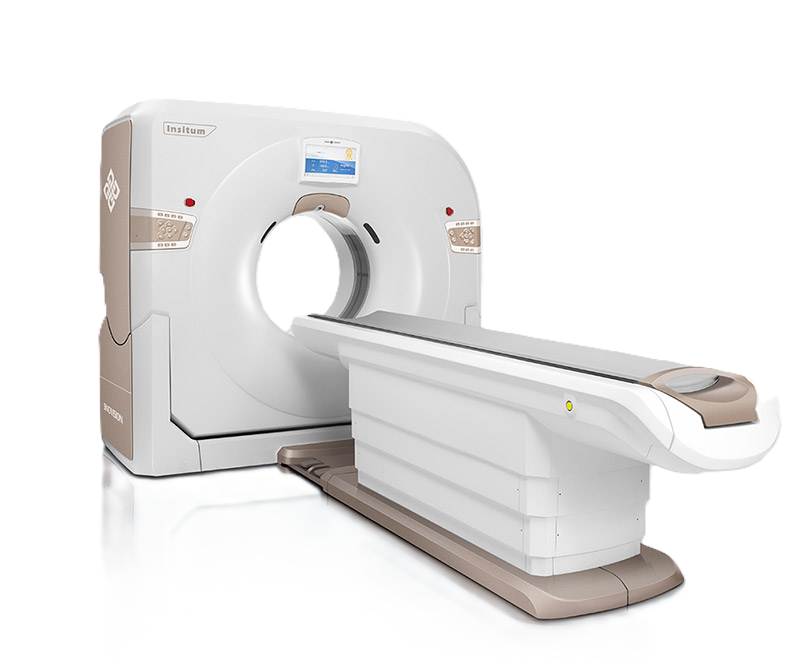

128-срезовый компьютерный томограф SinoVision InsitumCT 768

InsitumCT 768 является вершиной нового поколения широкоапертурных широкополосных компьютерных томографов. Этот КТ-сканер обеспечивает 128 срезов КТ при апертуре 76 см, увеличивая производительность визуализации до 21 л/см, способствуя точной диагностике и лечению заболеваний и значительно улучшая клинические характеристики и масштабируемость. Обеспечивает получение изображений высокого разрешения при низкой дозе облучения.

Компьютерный томограф Insitum CT 768 – старшая модель в линейке SinoVision Insitum. Еще более быстрый и еще более мощный, он значительно повышает пропускную способность кабинета КТ, обеспечивая при этом высококачественные исследования даже в самых сложных случаях практически во всех областях, включая кардиологию, исследования сосудистой системы, онкологию. Имеет специализированный педиатрический протокол исследования, минимализирующий лучевую нагрузку на ребенка.

Томограф InsitumCT 768 оснащен запатентованным высокоэффективным детектором Micro Wafer.

Гентри

- Апертура: 76 см

- Наклон: 30 градусов

- Поле зрения: 50 см

Стол пациента

- Ширина стола: 42 см

- Максимальная нагрузка: 250 кг

- Перемещение по горизонтали: 1950 мм

- Скорость перемещения: 5 мм в секунду

- Высота стола в самом низком положении: 425 мм

- Подъем по вертикали: 565 мм

- Особенности: Управление с пульта, аксессуары для фиксации и укладки